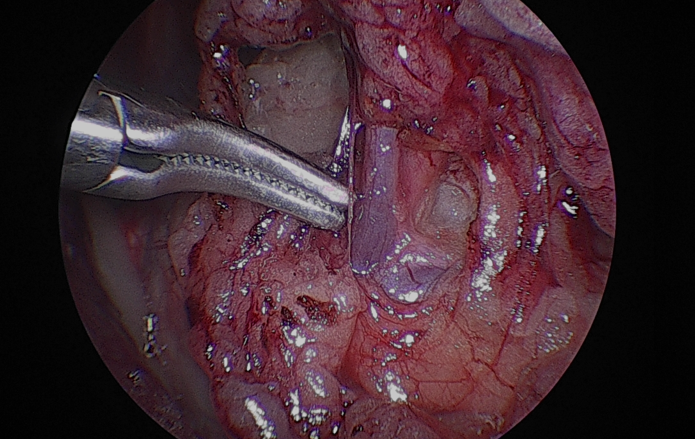

환자는 고령이었기 때문에 수술 후 통증과 회복 부담을 최소화하고자 복강경을 이용한 최소침습적 신장적출술을시행하였습니다.수술 과정은 다음과 같이 진행되었습니다.먼저종양이 위치한 신장을 후복막에서주변 조직과 분리하였습니다.

신장을 충분히 노출한 뒤, 신혈관을 순차적으로 처리했습니다.우선신정맥을 둔성으로박리하여 분리한 뒤, 클립으로 결찰하고절단하였습니다.

이어서 신동맥역시 같은 방법으로 둔성박리 후 클립 결찰후 절단하였습니다.

그 다음 신장에서 이어지는 요관을 따라 원위부로 추적하여 방광에 가까운 지점에서 둔성분리한 후 클립으로 결찰하고절단하였습니다.

이렇게 신장, 혈관, 요관이 모두 안전하게 분리된 것을 확인한 뒤, 적출된 신장을 수거 백에넣어 복강 내 오염 없이 외부로 제거하였습니다.

최소침습적 접근을 통해 조직 손상을 줄이고 통증을 최소화하면서, 종양을 안전하게 제거하는 데 중점을 두고 수술을 진행하였습니다.